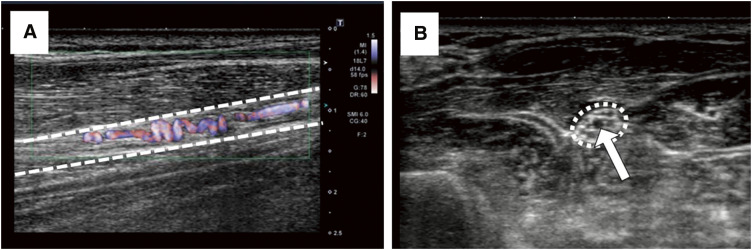

目的:据报道,血栓闭塞性脉管炎(Buerger 病)是一种难治性血管疾病,表现为远端动脉血栓形成,偶尔出现静脉闭塞,血栓和血管壁出现炎性变化。患者往往因肢体坏死而需要截肢。开瓶器(CS)是一种小动脉盘绕,是一种重要的诊断发现,主要通过血管造影发现。不过,最近也可以通过现代超声波技术发现它。方法:在 48 个研究区域的 22 个病例中,我们使用超声波技术识别 CS,从而观察其与周围神经和动脉的关系。结果:在所有病例中,我们都能确定 CS 的位置:在所有病例中,我们都能很容易地识别出 CS,并确认 CS 和神经都被带入鞘中。CS 的位置存在于闭塞的主动脉周围以外的区域,一些 CS 在神经内部(16 个区域),一些 CS 在神经外部(10 个区域),这表明 CS 作为侧支供血血管起作用,具有发达的正常血管样解剖结构。结论我们在观察 CS 时,不仅要观察主干动脉周围,还要观察神经主要流经的区域,即使它们没有伴随主干动脉。(本文译自 Jpn J Vasc Surg 2023; 32: 345-350)。

Objective: Thromboangiitis obliterans (Buerger disease) is known as an intractable vascular disease that has been reported as thrombosis in distal arteries and occasional venous occlusion, as well as inflammatory changes in the thrombus and vascular wall. Patients often require limb amputation due to limb necrosis. Corkscrew (CS), a small arterial coiling, is an important diagnostic finding that was mainly found with angiography. Recently, however, it can also be identified using a modern ultrasonographic technique. Methods: In these 22 cases, in 48 areas of study, we used the ultrasonographic technique to identify the CS, which allowed us to observe its relationship with the surrounding nerves and arteries. Results: In all cases, it was possible to identify the CS easily and it was confirmed that the CS and the nerve were carried down in their sheath. The sites of the CS existed in areas other than the area around the occluded main arteries and some CS that ran inside the nerve (16 areas) and some CS that accompanied the outside of the nerve (10 areas) were confirmed, suggesting the CS work as collateral blood supply vessels, with well-developed normal vessel-like anatomy. Conclusion: When we observe the CS, it is important to observe not only around the main trunk artery but also areas where nerves mainly run, even if they do not accompany the main trunk artery. (This is a translation of Jpn J Vasc Surg 2023; 32: 345-350.).